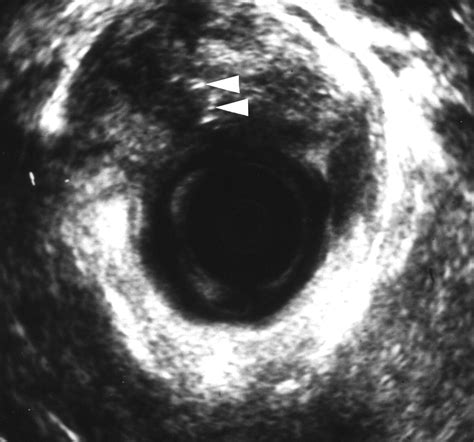

During a consultation, a colorectal surgeon will perform a physical examination. In some cases, they may use diagnostic imaging to visualize the tract that cannot be seen with the naked eye. Procedures such as endorectal ultrasound or pelvic MRI are far more informative than general Rectal Fistula Images found on public forums, as they provide a clear map of the anatomy for the surgeon.